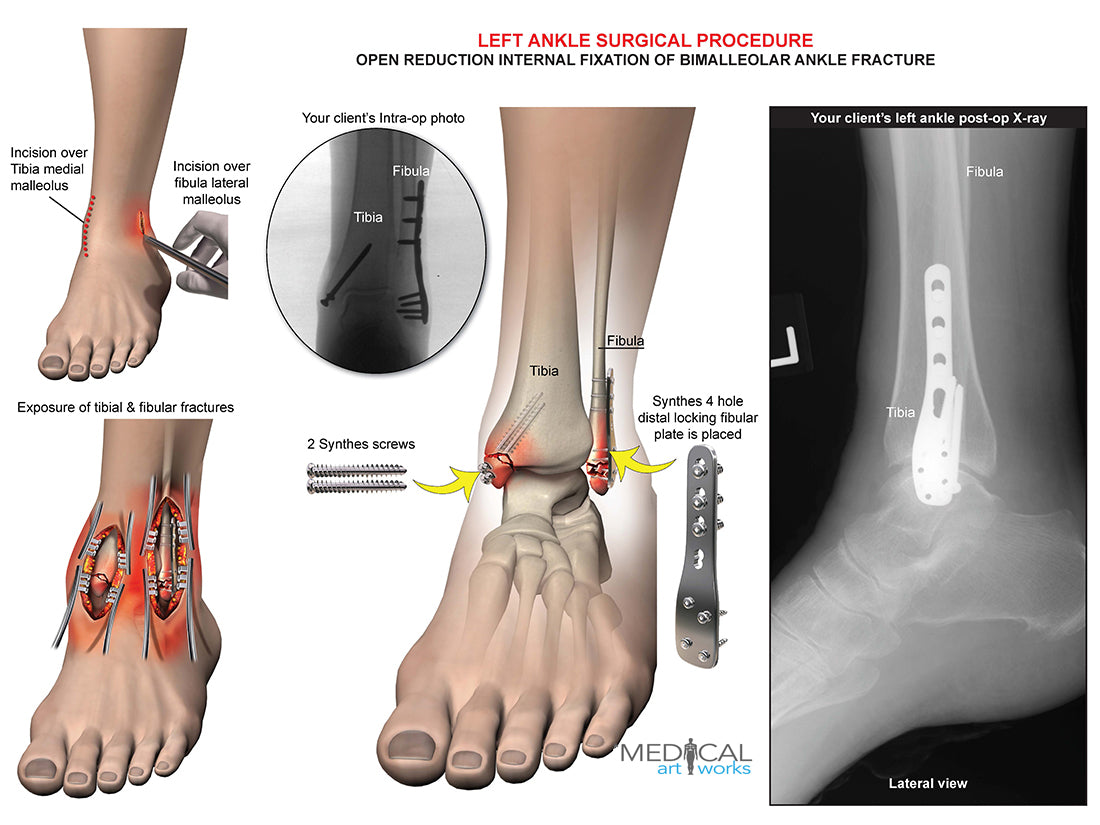

Left ankle and tibia bimalleolar fracture -ORIF

Left ankle and tibia bimalleolar fracture -ORIF

Open reduction internal fixation of bimalleolar ankle fracture. Synthes 4 hole distal locking fibular plate is placed, 2 Synthes screws. Add you own client's post-op x-ray.